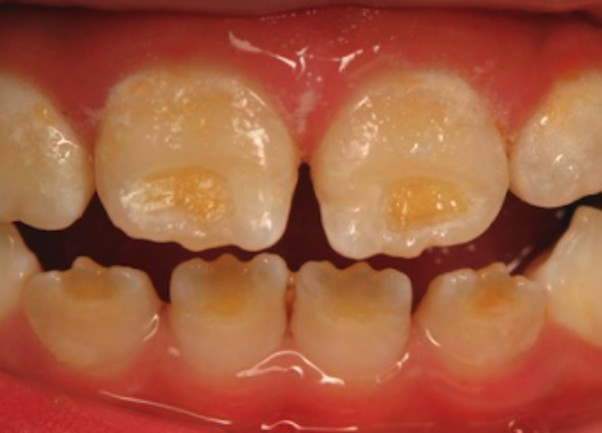

Enamel is the hard, protective outer layer of your teeth. Enamel hypoplasia is a defect of the enamel that only occurs while teeth are still developing. Still, it can affect both baby teeth and permanent teeth. The condition results in thin enamel, which makes your teeth vulnerable to dental decay.

The visual signs of enamel hypoplasia include white spots, pits, and grooves on the outer surface of the teeth.

pits, tiny groves, depressions, and fissures

white spots

yellowish-brown stains (where the underlying layer of dentin is exposed)

sensitivity to heat and cold

lack of tooth contact, irregular wearing of teeth

susceptibility to acids in food and drink

retention of harmful bacteria

increased vulnerability to tooth decay and cavities.